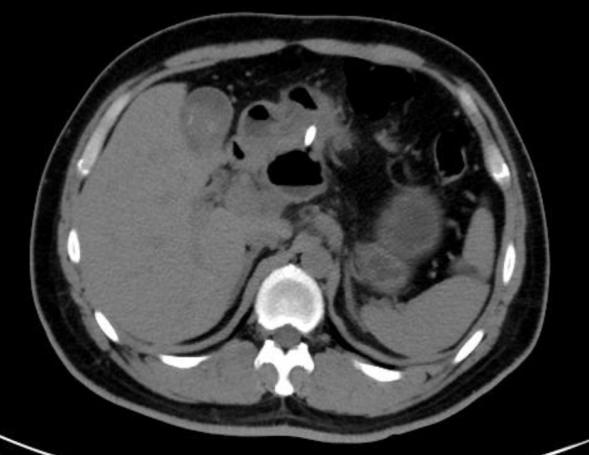

近日,我院鹿泉院区消化内科团队成功实施首例超声内镜引导下的胰腺假性囊肿穿刺支架引流术,为一名中年男性重症急性胰腺炎患者解决了胰头假性囊肿问题,标志着该科室在胆胰疾病诊疗特别是超声内镜介入诊疗技术领域迈...